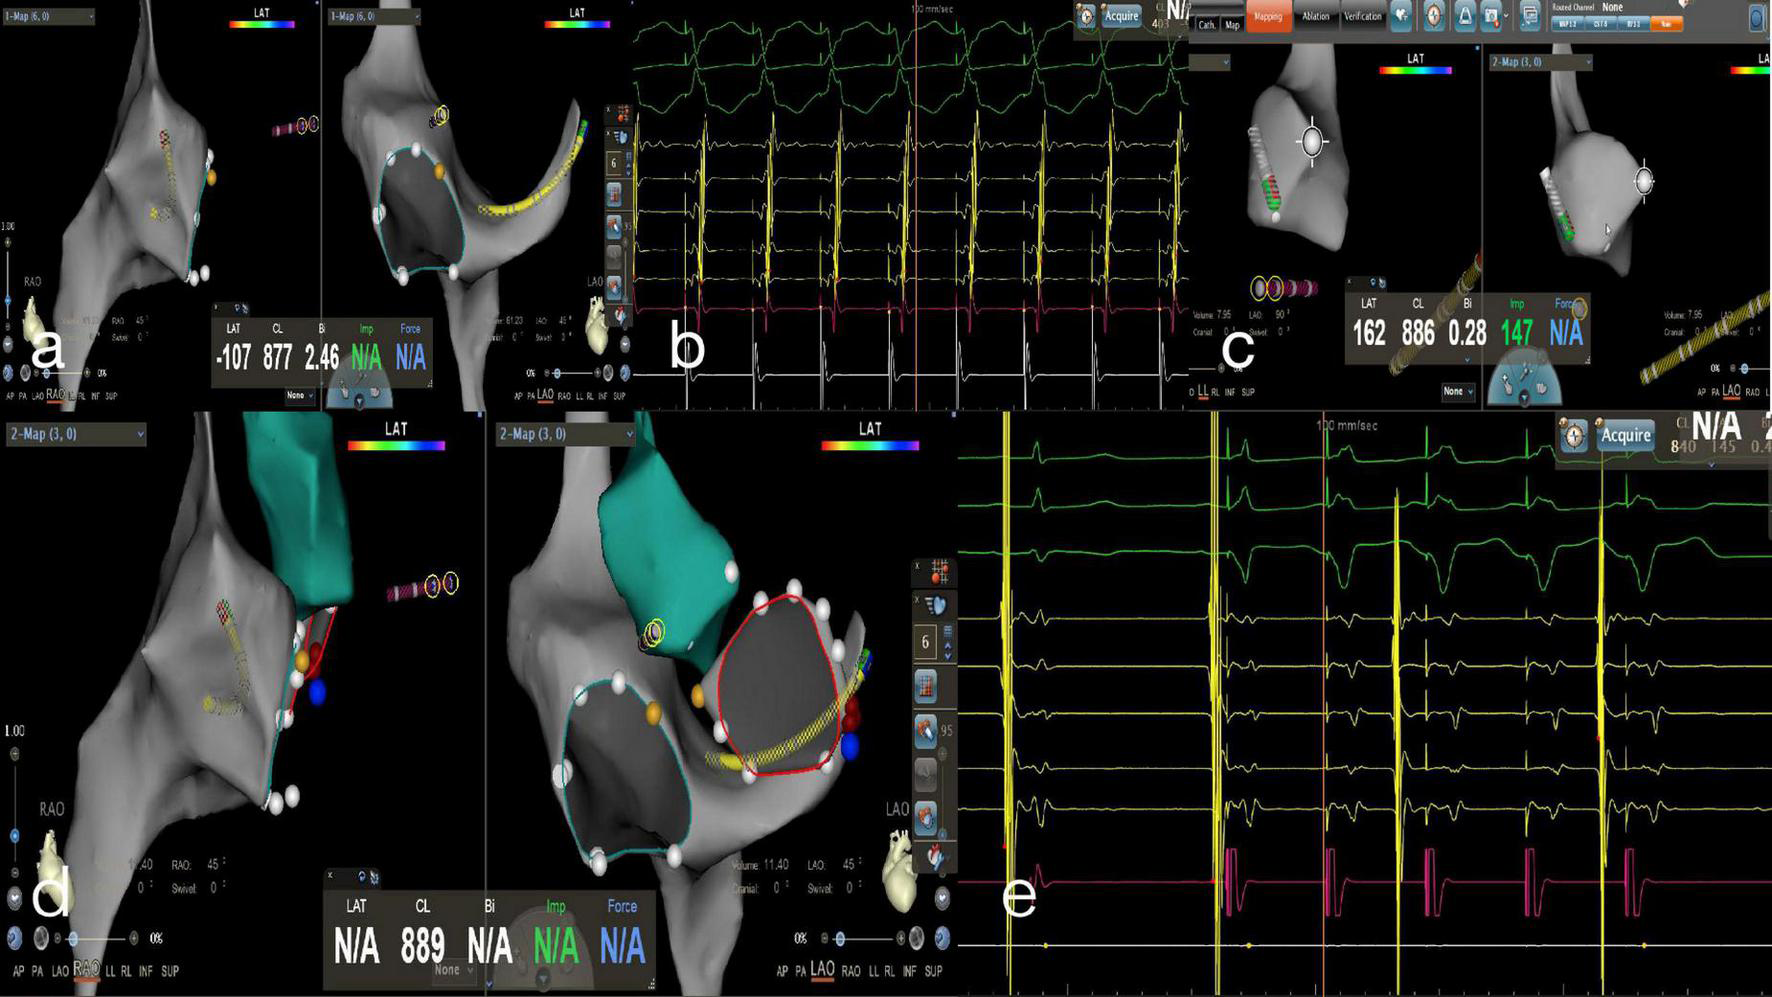

FIGURE 4

Zero-fluoroscopy radiofrequency ablation for AVRT. (a) Modeling of the right atrium was performed with a Decanav catheter using the CARTO 3 System. The Decanav catheter was placed in the coronary sinus and a quadripolar catheter was placed in the apex of the right ventricle. (b) During the onset of SVT stimulated by S1S1, the retrograde A wave showed eccentric conduction and was diagnosed as a left concealed accessory pathway. (c) The retrograde aortic method was used to deliver the ablation catheter to the aortic root and establish a model of the aorta. (d) The ablation catheter electrode crosses the aortic valve to model the mitral annulus, and the ablation target is located at three o’clock. (e) An electrophysiology study showed ventricular pacing with ventricular-atrial separation and retrograde transmission through atrioventricular node. The retrograde A wave was centripetal.